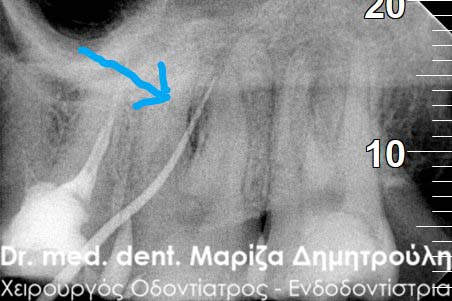

Έγινε η κλινική και ακτινογραφικά εξέταση του δοντιού. Στην αρχική ακτινογραφία που πραγματοποιήθηκε πριν τη διάνοιξη του δοντιού παρατηρήθηκε ο έντονος εκτροχισμός του δοντιού ανάμεσα στις ρίζες. Η ακτινογραφική αυτή εικόνα γεννά υποψίες για πιθανή διάτρηση του δοντιού στο συγκεκριμένο σημείο. Διάτρηση ενός δοντιού κατά τη διάρκεια της απονεύρωσης μπορεί να προκληθεί όταν ο οδοντίατρος “ανοίγει” (τροχίζει) το δόντι στην προσπάθεια του να εντοπίσει τις ρίζες του δοντιού (ριζικοί σωλήνες). Είναι δηλαδή πιθανόν το δόντι να τροχιστεί σε άλλο σημείο από αυτό που εντοπίζονται οι ρίζες του δοντιού, με αποτέλεσμα να δημιουργηθεί μία τρύπα στο δόντι. Η τρύπα αυτή ονομάζεται διάτρηση.

Μετά από τη χορήγηση τοπικής αναισθησίας και την τοποθέτηση ελαστικού απομονωτήρα ακολούθησε η διάνοιξη του δοντιού. Αμέσως μετά την αφαίρεση του προσωρινού σφραγίσματος παρατηρήθηκε έντονη και απότομη αιμορραγία του δοντιού, η οποία προερχόταν από ένα συγκεκριμένο σημείο. Η κλινική αυτή εικόνα επιβεβαίωσε τις υποψίες για διάτρηση του δοντιού. Εντοπίστηκε το σημείο της διάτρησης και έγινε έλεγχος με μία ακτινογραφία. Στη συνέχεια πραγματοποιήθηκε η αποκατάσταση της διάτρησης με ειδικό υλικό και εντοπίστηκε ο τρίτος σωλήνας του δοντιού. Η όλη διαδικασία επιβεβαιώθηκε με τη λήψη ακτινογραφίας.

Επιβεβαίωση της διάτρησης